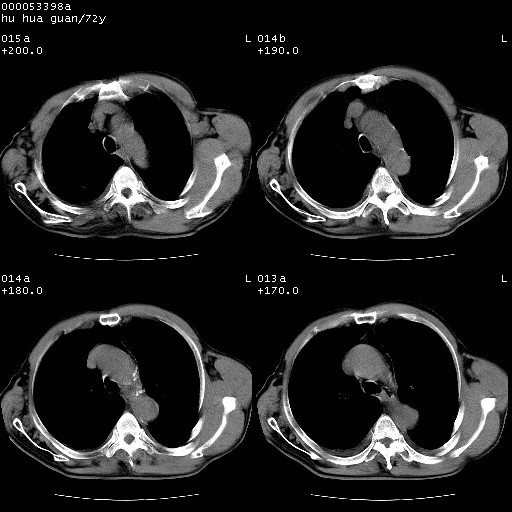

1、右上肺结节病变,肺泡癌不除外,请随诊;左下肺近后纵隔病变,考虑纵隔型肺癌侵犯大血管可能;

2、右下肺背段少许炎症,双侧胸腔积液,右下肺纤维索条。

降主动脉前移位,后纵隔占位

后纵隔占位,降主动脉前移位;双侧胸腔积液;应排外食管病变侵犯血管可能;

可以明确的说。肯定不是主动脉夹层破裂出血!考虑为淋巴瘤或间叶组织来源的恶性肿瘤可能性大。右肺小结节建议薄层观察,如能发现恶性征象,那椎前改变就考虑为转移所致。至于双侧少量胸水乃静脉血回流受阻所致。

1、右肺周围性肺癌、胸腔积液(双)

3、后纵隔淋巴类肿瘤